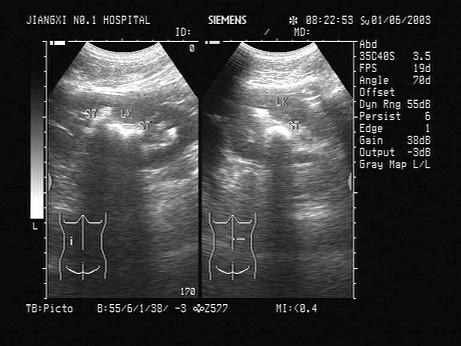

女性,出现腰痛并血尿3天,超声检查如图所示,该病例最可能诊断?(?)A.肾钙质沉积症B.肾结石C.肾内钙化灶D.肾窦灶性纤维化E.海绵肾